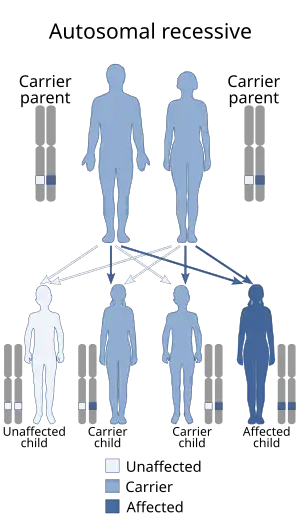

| This condition is inherited in an autosomal recessive manner. | |

This syndrome is caused by pathogenic variants (mutations) in the VPS13B gene at chromosomal locus 8q22.[2] It has an autosomal recessive transmission with variable expression.[3] Variants in VSP13B also cause Mirhosseini–Holmes–Walton syndrome, which is now considered to be the same entity as Cohen syndrome.[4][5][6]